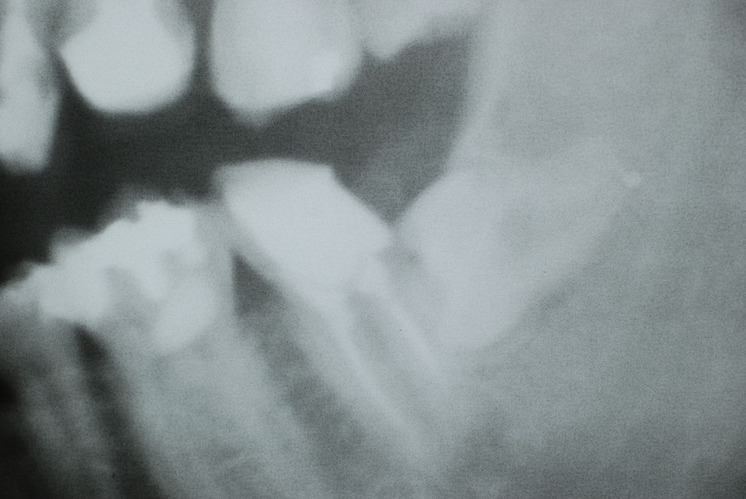

下記は患者に言われるままに血だらけでの不潔な状態で虫歯をとり埋めたようで全然適合していませんし、外れそうになっていました。

外したところです。中は虫歯のオンパレードでした。